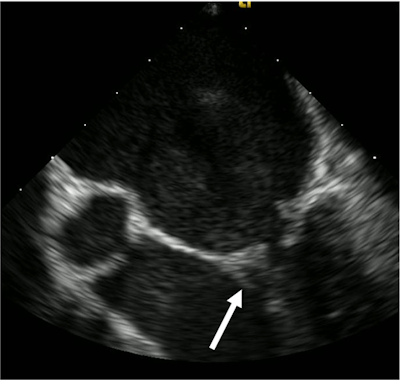

A transesophageal echocardiogram of the man revealed vegetation, an infected mass growing on a heart valve that is a hallmark of infective endocarditis. This is believed to be the first known case of the disease stemming from robust flossing, according to the authors.

Three separate blood cultures collected 15 minutes apart yielded S. gordonii. A transthoracic echocardiogram (TTE) didn't show anything remarkable, but a transesophageal echocardiogram (TEE) revealed a small vegetation on the posterior leaflet of the mitral valve. His antibiotics were changed to 242 mg of intravenous gentamicin every 24 hours and 24 million units of penicillin G continuous infusion, due to the sensitivities of S. gordonii, the authors wrote.